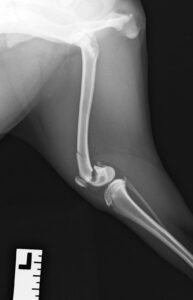

9ヶ月の柴犬の女の子が、高所から落下してしまい左後肢を痛めたとのことで来院されました。左後肢は足を着くことができず、レントゲン検査の結果、大腿骨(太ももの骨)の複雑骨折を認めました。

大腿骨の膝に近い部分が骨折してしまっており、さらに単純な骨折ではなかったため、内側と外側にそれぞれプレートを設置し固定しました。

大腿骨遠位の骨折は特に若齢の犬猫においてしばしば発生します。若齢時には多くの骨の両端に成長板という骨を作る場所があり、その場所は強い力がかかった際に骨折しやすいためです。単純な骨折の場合にはピンだけで整復が可能なことも多くありますが、今回のような状況ではプレート固定も適応になります。どちらにしても手術後に関節の拘縮が起きやすく、術後のリハビリも重要になってきます。当院ではリハビリに特化したスタッフも在籍し、術後のケアもご家族と共に実施していきますので安心して手術を受けて頂くことができます。